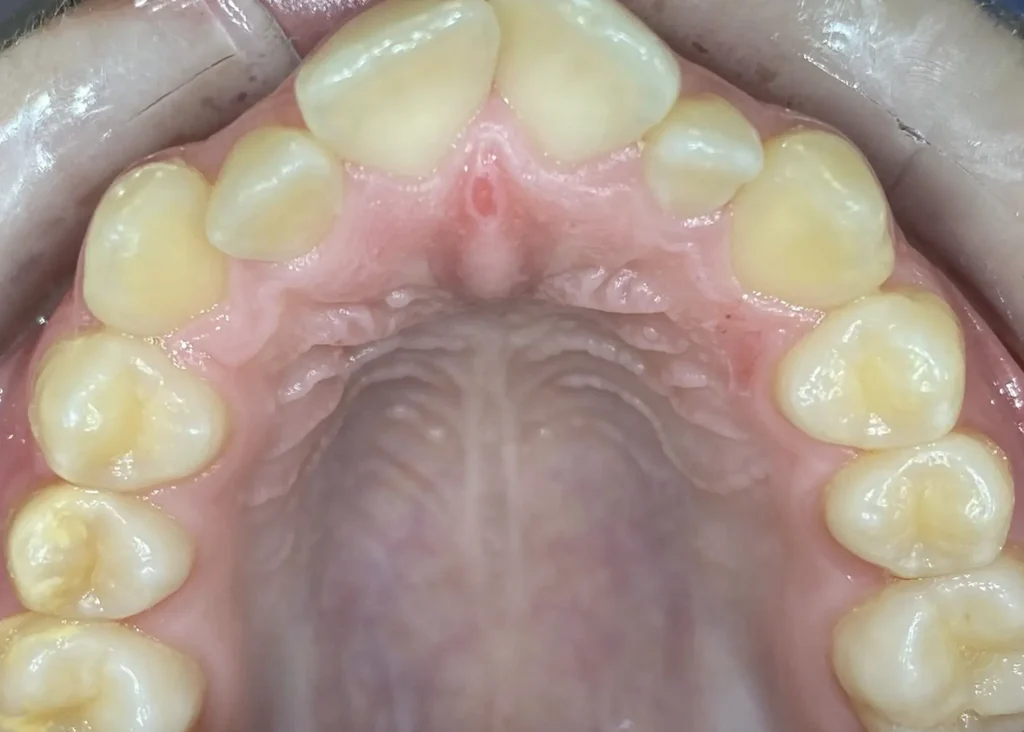

La ortodoncia invisible o Invisalign Ferrol es una técnica de ortodoncia basada en alineadores transparentes, mediante la que se pueden mover y recolocar las piezas dentales tras realizar una predicción a través de un sofisticado software de tecnología 3D que escanea la boca del paciente.

Casos clínicos de ortodoncia en CDPA